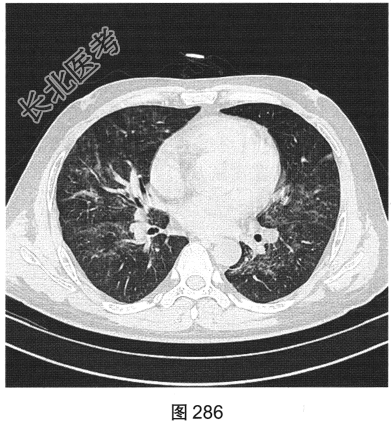

- [材料题] 患者男性,33岁,因“双下肢散在皮下出血点伴尿检异常3个月余,咳嗽、胸闷伴发热一周”就诊。患者脂肪肝、胆囊炎,服用莲葡双清片;随后几日内食用淡水鱼、鱿鱼、饮啤酒;5天后出现双下肢散在皮下出血点,未重视;10天后出现腹痛,在当地医院检查尿中有蛋白、定量不详,血常规检查正常,肾功能正常,应用醋酸泼尼松效果欠佳,行肾活检术,病理诊断:紫癜性肾炎,继发IgA肾病。患者每天静脉滴注甲泼尼龙0.5g,共3天,后改为口服甲泼尼龙28mg/d,共35天。一周前着凉后出现咳嗽、胸闷伴发热,体温达39.1℃,于当地医院抗炎治疗效果欠佳,遂来本院。实验室检查:血白细胞计数6.92×109/L,中性粒细胞0.845,CRP为2.7mg/dl。患者PP65阳性。胸部CT检查如图284~图287所示。

- 多项选择题2.根据患者病史和影像特征,您的诊断是( )

A、肺结核

B、巨细胞病毒感染

C、急性肺泡损害

D、外源性过敏性肺泡炎

E、肺水肿

F、肺孢子菌感染